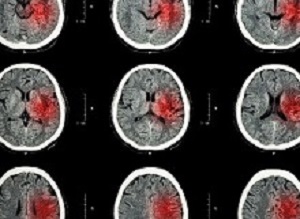

Electroencephalographies (EEGs) of the patients clearly showed an increase in the number of connections among the motor cortex regions of their damaged brain hemisphere, which corresponded with the increased ease in carrying out the associated movements. What's more, the enhanced motor function didn't seem to diminish with time. Evaluated again 6-12 months later, the patients hadn't lost any of their recovered mobility.

Brain-computer interfaces (BCI) are used in stroke rehabilitation to translate brain signals into intended movements of the paralyzed limb. However, the efficacy and mechanisms of BCI-based therapies remain unclear. Here we show that BCI coupled to functional electrical stimulation (FES) elicits significant, clinically relevant, and lasting motor recovery in chronic stroke survivors more effectively than sham FES. Such recovery is associated to quantitative signatures of functional neuroplasticity. BCI patients exhibit a significant functional recovery after the intervention, which remains 6–12 months after the end of therapy. Electroencephalography analysis pinpoints significant differences in favor of the BCI group, mainly consisting in an increase in functional connectivity between motor areas in the affected hemisphere. This increase is significantly correlated with functional improvement. Results illustrate how a BCI–FES therapy can drive significant functional recovery and purposeful plasticity thanks to contingent activation of body natural efferent and afferent pathways.